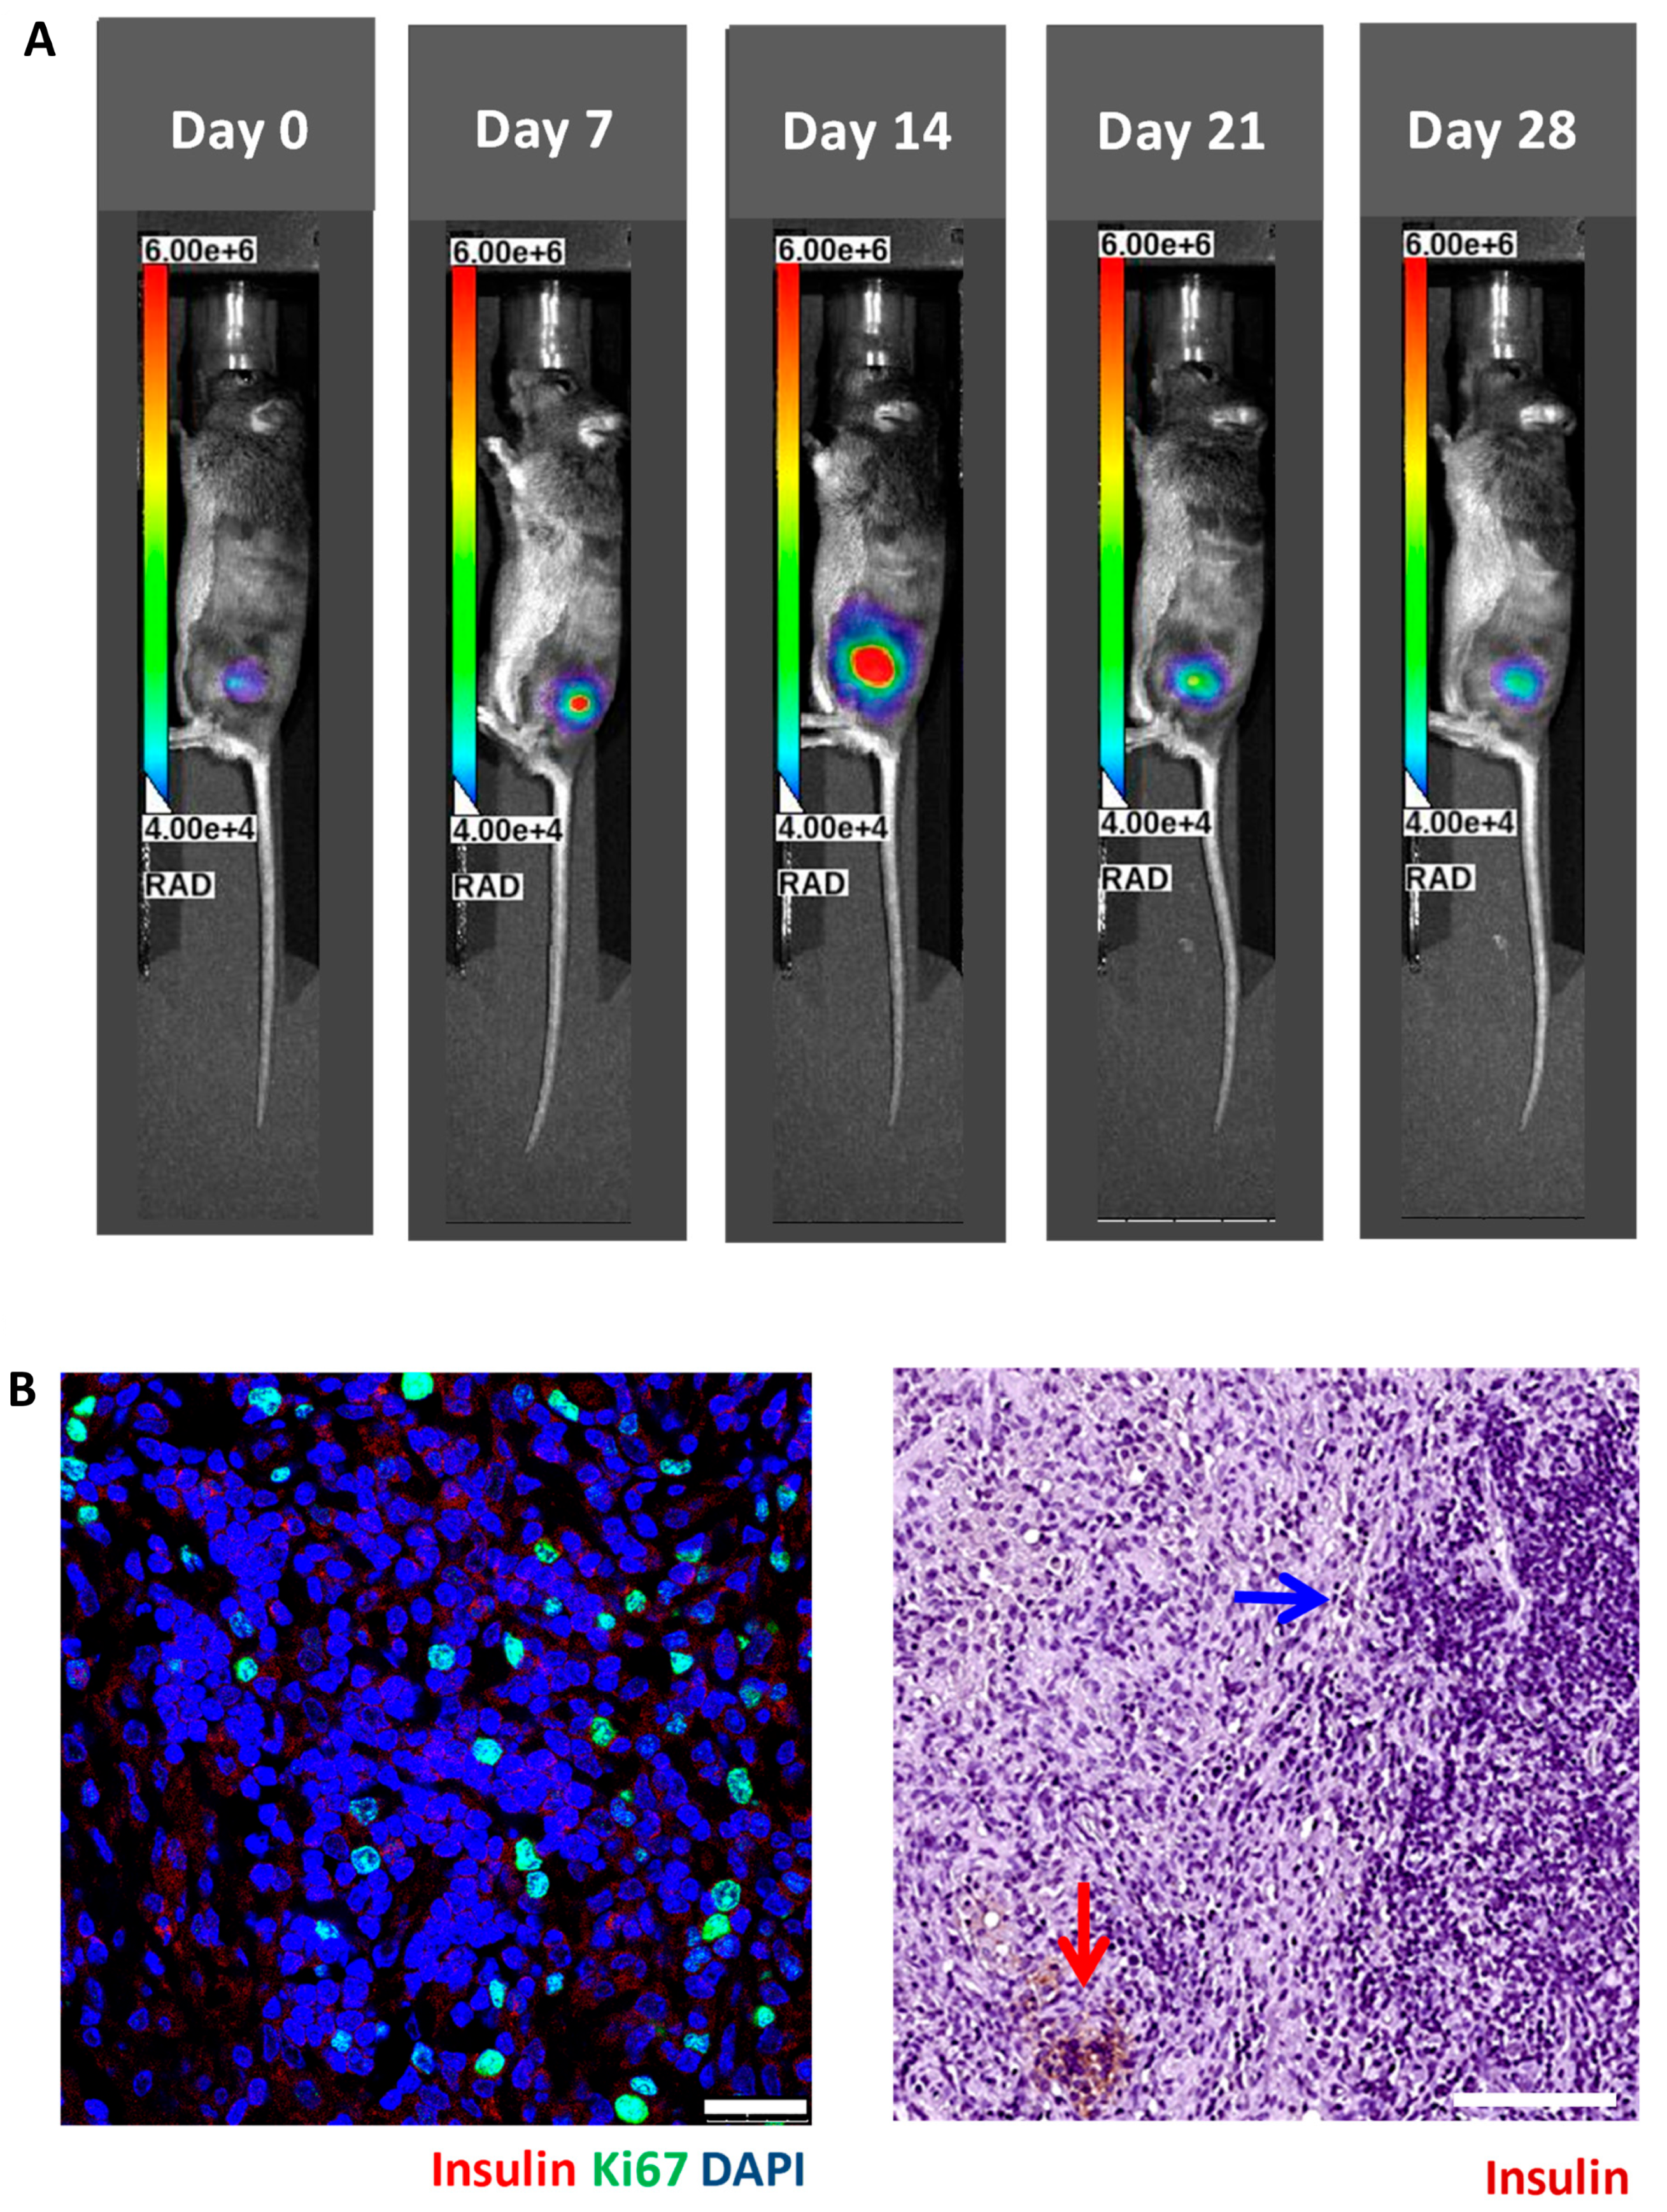

3.2. In Vivo Bioluminescence Imaging of Matrigel-Embedded MIN6 Cells Subcutaneously Transplanted in Nude and C3H Mice

3.3. Histology of Subcutaneous Matrigel-Embedded MIN6 Cell Grafts in Nude and C3H Mice